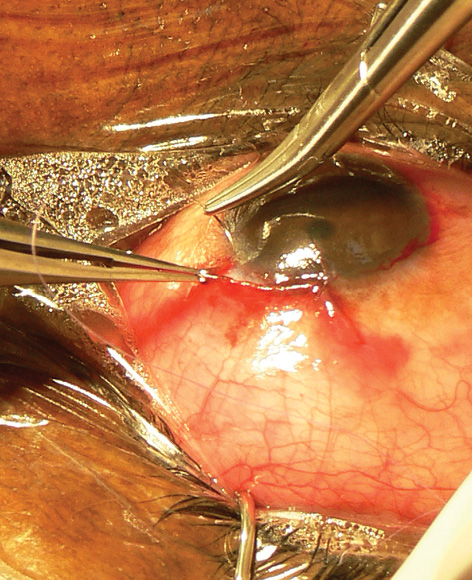

Figure 1. Interrupted suture closure using a spatula needle and absorbable suture material.

- closure, such as placing sutures of precise tension to approximate a scleral flap or ensuring a watertight conjunctival closure (Figures 1 and 2)